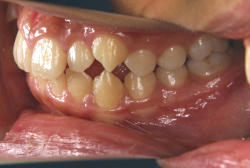

上顎前突

上顎前突(出っ歯)とは上顎が前に出ている状態です。この症状の特徴は、上下の歯並び全体の位置関係が相対的に上顎が優位になっていて、前歯が外に反っているだけでなく奥歯の位置関係も上が前にズレています。さらに凸凹の症状も合併していることがよくあり、上の前歯の見た目を気にして来院する方が多いのですが、実は今言った理由で噛み合わせにも異常があるため、このまま放置すると顎関節症という症状が出ることもあります。

「出っ歯を治したい」という主訴で来院したケースです。診断の結果、「2級1類の上顎前突+軽度叢生」と判明しました。2級というのは、基本的に出っ歯の噛み合わせになっていることを言います。その中でも上の前歯が著しく外に反っているケースを、「1類」といいます。初診時の横向きの写真を見ると、それがはっきり分かります。上の前歯に押されて唇も膨らんで、審美線をかなりオーバーしています(審美線とは、鼻の先端と顎の先端を結ぶ線のことで、この線よりも唇は内側にある方が良いとされています)。

このような症状の場合は、前歯を内側に入れるためにかなり大量の隙間を必要とします。通常は上下左右の小臼歯を抜歯させていただくのが正解です。治療後は歯の角度が正しくなっただけでなく、唇の審美性が大幅に改善しました。もちろん噛み合わせ的にも正しい状態が確立しています。